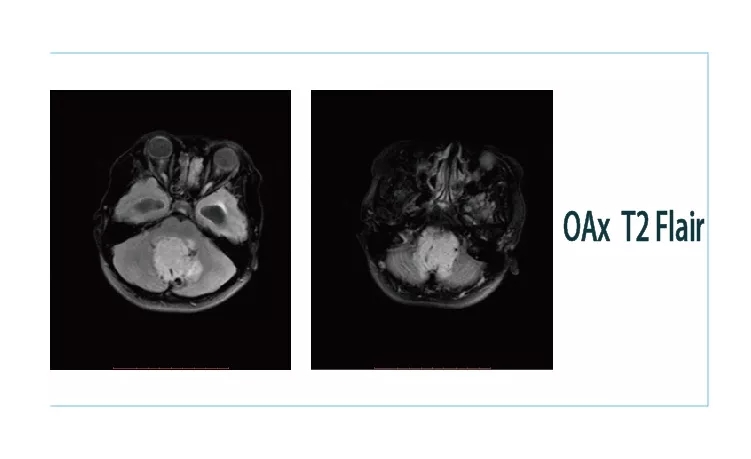

【朗润影像档案】20181026磁共振影像病例结果讨论